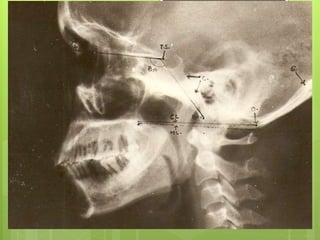

CRANIOMETRY:

 Craniometry of the CVJ uses a series of lines, planes &

angles to define the normal anatomic relationships of

the CVJ.

 These measurements can be taken on plain X rays,

3D CT or on MRI.

 No single measurement is helpful.

 disadvantage --anatomic structures and planes vary

within a normal range.

The important lines are

1. Chamberlain’s line

2. Wackenheim’s clivus

canal line

3. Mc Gregor’s line (basal

line)

4. Mc rae’s line ( foramen

magnum line)

5. Height index of Klaus

6. Boogard,s line

7. FISHGOLD’S DIGASTRIC

LINE

8. FISHGOLD’S BIMASTOID